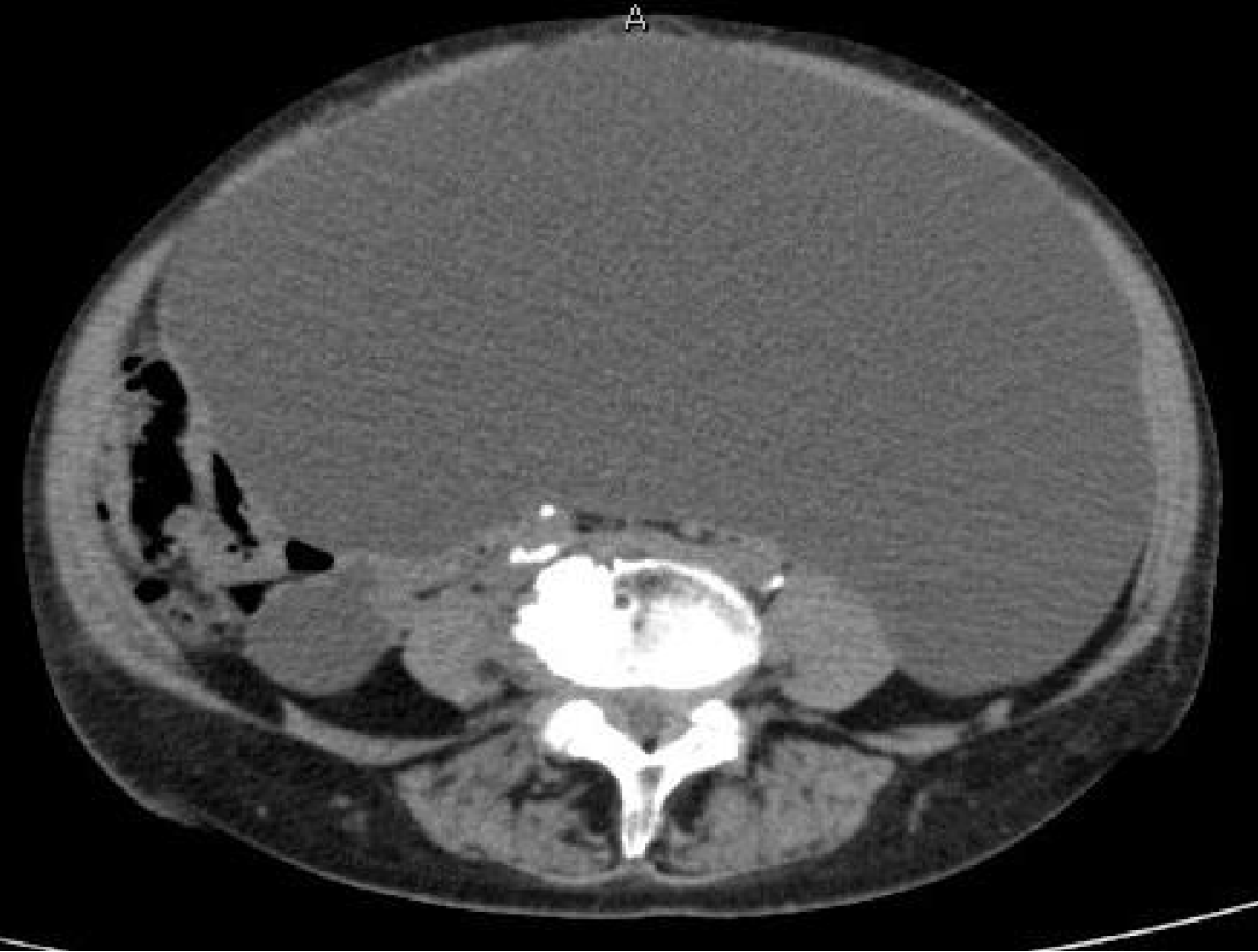

Figure 1 Pelvic computed tomography image a giant cystic mass measuring 30 cm in its longest diameter and extending to the area above the umbilicus was observed.

No clustered cystic formations, solid components, or irregular septa were detected within the tumor.